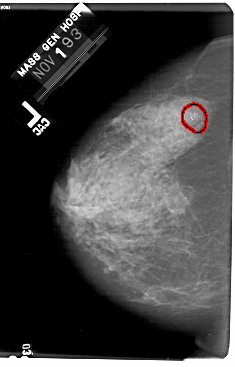

FILE: A_1732_1.LEFT_CC.OVERLAY

TOTAL_ABNORMALITIES 1

ABNORMALITY 1

LESION_TYPE CALCIFICATION TYPE AMORPHOUS DISTRIBUTION CLUSTERED

ASSESSMENT 2

SUBTLETY 4

PATHOLOGY BENIGN

TOTAL_OUTLINES 1

BOUNDARY